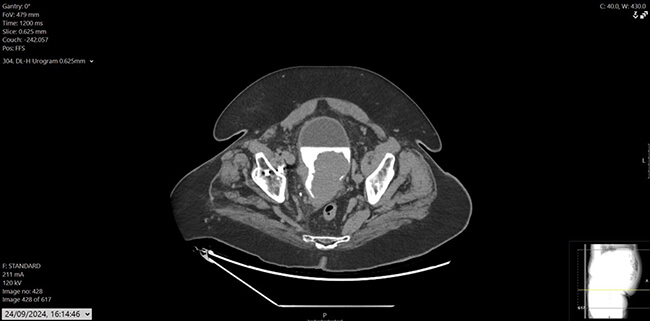

Figure 2: CT urogram, axial.